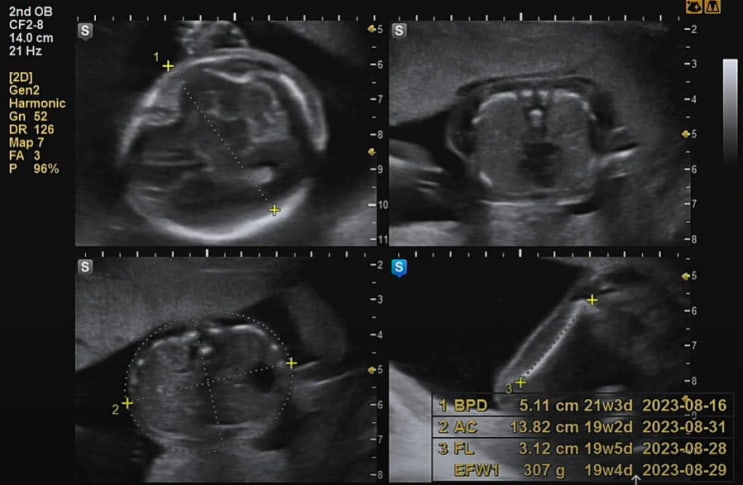

임신 16주차 6일, 입덧도 나아지고 그새 쑥 자랐네167g :)

안정기에 접어들고 입덧도 괜찮아지니 입맛이 돌아왔다. 빠졌던 몸무게도 원상복구 됐다. 임신 16주 정기검...